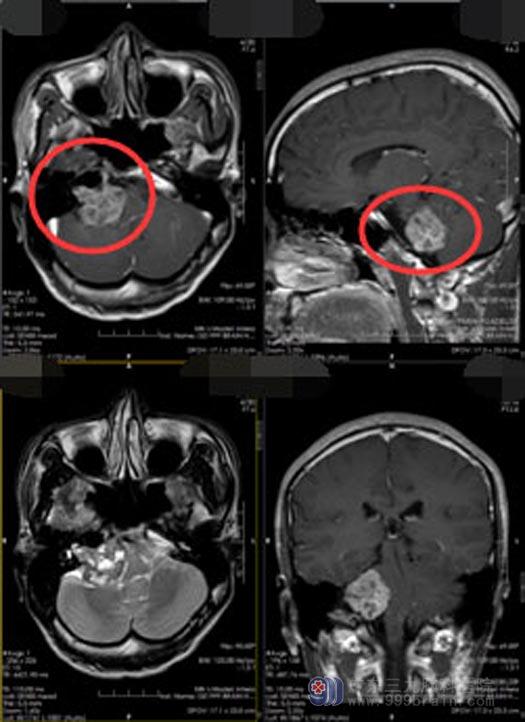

近1周,龙先生感觉右侧面部放电样疼痛较之前加重,讲话、吞咽都可以诱发,疼痛导致龙先生无法正常吃饭、睡觉,忍受不了的龙先生又在医院做了更进一步的检查,头颅MR提示“右侧桥小脑角占位性病变,考虑听神经鞘瘤”。

知道结果后的龙先生每天都忐忑不安,他通过各种途径搜集疾病资料,了解到:听神经瘤起源于听神经,属良性,缓慢增长,逐渐影响听力,引起耳鸣,甚至听力丧失,随着肿瘤增大,有些患者还伴发三叉神经受累,感觉面部麻木或疼痛,以及面神经受累,出现口角歪斜等症状。手术切除肿瘤是首选的治疗方法,最终,龙先生选择了广东三九脑科医院的神经外五科。

住院期间,龙先生认识了很多病友,看到他们都能开开心心地出院,龙先生也增强了自己战胜疾病的信心。由医院副院长、神经外五科主任主刀在全麻下行“右侧桥小脑角区听神经鞘瘤”切除术,手术非常顺利,肿瘤切除干净。术后,龙先生面部疼痛症状消失,听力也有改善,没有出现手术并发症。

▲手术前